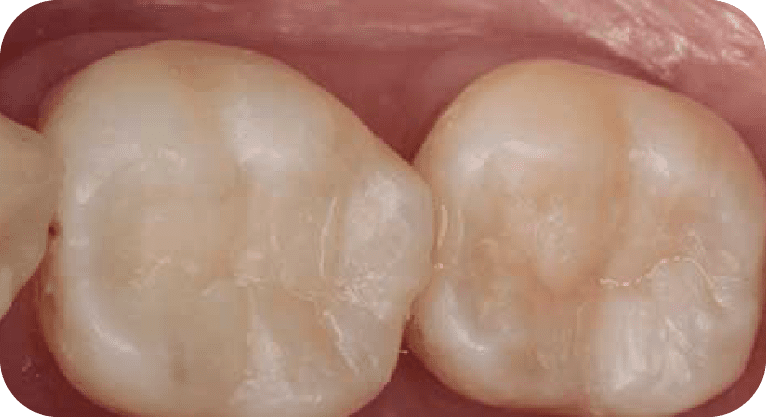

Male patient, “25” years old

Treatment: Root canal treatment

The patient had pain in two molars due to deep cavities. Root canals were performed on both teeth, disinfecting and sealing the canals, followed by zirconia crowns to restore their function.